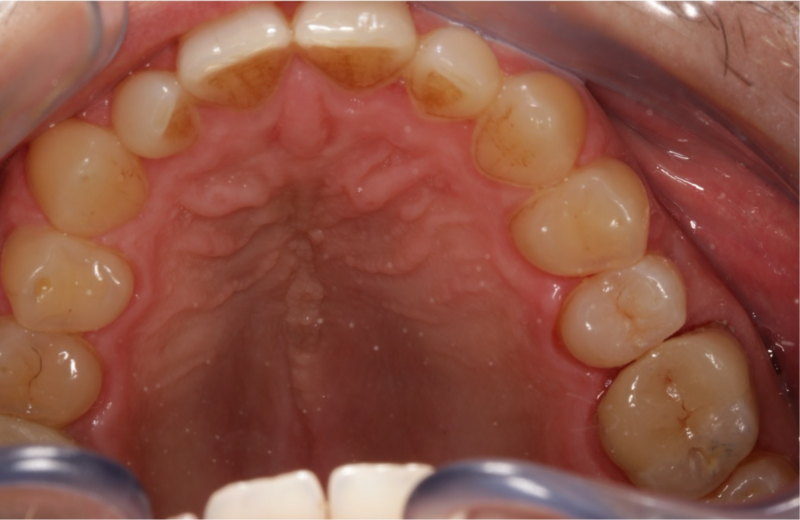

situation finale

Situation finale après collage et polissage.

Après